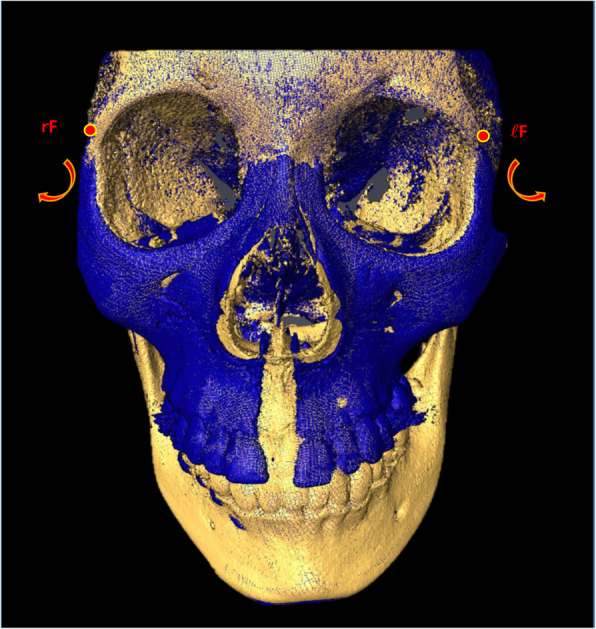

I'm 19. And I'm currently consulting with an Australian maxillofacial surgeon about getting a LeFort I/BSSO+genioplasty and a LeFort III. I believe I'm the most deformed looking Asian person to ever set foot on this site. Every bone of my face lacks forward growth.